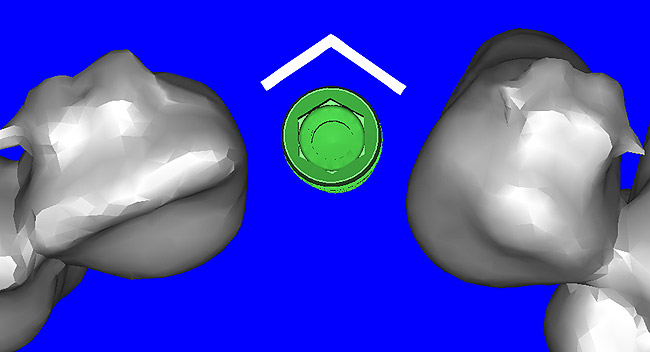

Using different masking (segmentation) and threshold Hounsfield unit values, several new 3D bone volumes can be created which offer invaluable information. To help determine the final position of each implant a new bone model was created with a Hounsfield unit value of 1480, which eliminated all but the densest objects included in the scan data. (Results may vary depending on the CBCT machine used.) The inner and outer layers of bone were removed, leaving the underlying enamel and root structure of the teeth (Figure 8A). After the bone had been stripped away, the root inclinations were examined closely. The most striking findings confirmed the rotated position of the right central, while revealing the slight mesial dilaceration of the root apex, which converged on the space needed for the path of the potential implant (Figure 8B). The schematic shapes of the proposed implants were visualized for the right and left lateral spaces in different rotations of the 3D maxillary arch. It was at this point that a determination was made as to the appropriate implant shape and type that would fit the available space while avoiding encroachment on adjacent tooth roots. A tapered design implant (Tapered Screw-Vent®, Zimmer Dental, www.zimmerdental.com) was chosen from the large virtual library. With the SIMPlant software, the virtual library contains data from dozens of implant manufacturers and realistic.computer-aided design representations as seen in Figure 9A through the translucent bone. The position of the left implant can be visualized with adequate mesial-distal distance between adjacent tooth roots (Figure 9B) and a more delicate placement (Figure 9C).

Figure 8a  By using the masking feature, the inner and outer layers of bone were removed virtually, revealing (A) the enamel and root structure of the teeth and the rotated position of the right central and (B) a slight mesial dilacerations of the root apex.

Figure 8a

Figure 8b  By using the masking feature, the inner and outer layers of bone were removed virtually, revealing (A) the enamel and root structure of the teeth and the rotated position of the right central and (B) a slight mesial dilacerations of the root apex.

Figure 8b